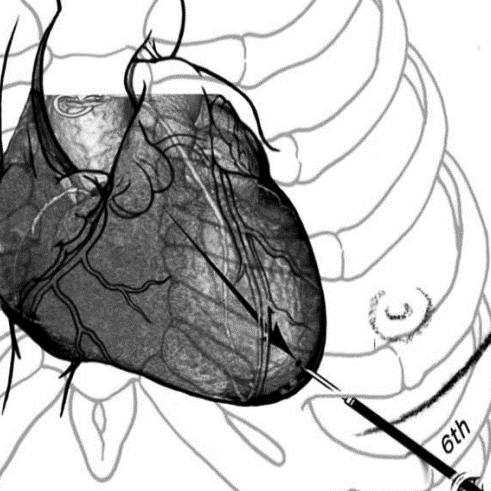

外科瓣膜置换术后瓣周漏(PVL)是人工心脏瓣膜置换术后特有的并发症,也是最常见的换瓣后再手术的原因。根据瓣周漏位置可以分为主动脉瓣瓣周漏、二尖瓣瓣周漏、三尖瓣瓣周漏、联合瓣膜瓣周漏,其中二尖瓣瓣周漏最为常见。相比再次开胸瓣周漏修补或再次换瓣手术,瓣周漏封堵创伤小,风险小,不需体外循环心脏停跳,是危重患者首选治疗方式。主动脉瓣瓣周漏好发部位多在外科视角4-9点位置,即右冠-右无交界位置;二尖瓣瓣周漏多见在外科视角9点和2点附近,即内外交界位置。主动脉瓣PVL封堵技术相对简单,二尖瓣PVL由于入路多弯操作相对难度大,需要根据患者具体解剖结构选择最优路径。

外科解剖学瓣周漏位置

二尖瓣瓣周漏封堵路径(左房顺行途径、左室逆行途径、经心尖入路途径)